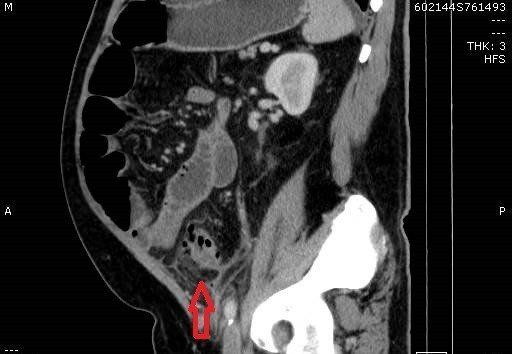

TC de abdome com contraste endovenoso fase excretora, evidenciando sinais de diverticulite aguda caracterizados por espessamento parietal do colon sigmoide, divertículos, densificação da gordura regional e presença de pequeno gás extraluminal, indicando pneumoperitônio discreto. Não há evidência de coleções pericolonicas associadas.

Na imagem, a diverticulite não complicada é caracterizada por filamento de gordura focal adjacente a um divertículo do cólon, geralmente o sigmóide. Uma pequena quantidade de líquido extraluminal e lóculos de gás podem estar presentes.

Encordoamento pericólico, muitas vezes desproporcionalmente proeminente em comparação com a quantidade de espessamento da parede intestinal

Espessamento segmentar da parede intestinal

Realce da parede do cólon

Perfuração diverticular

Extravasamento de gás e fluido para a pelve e cavidade peritoneal